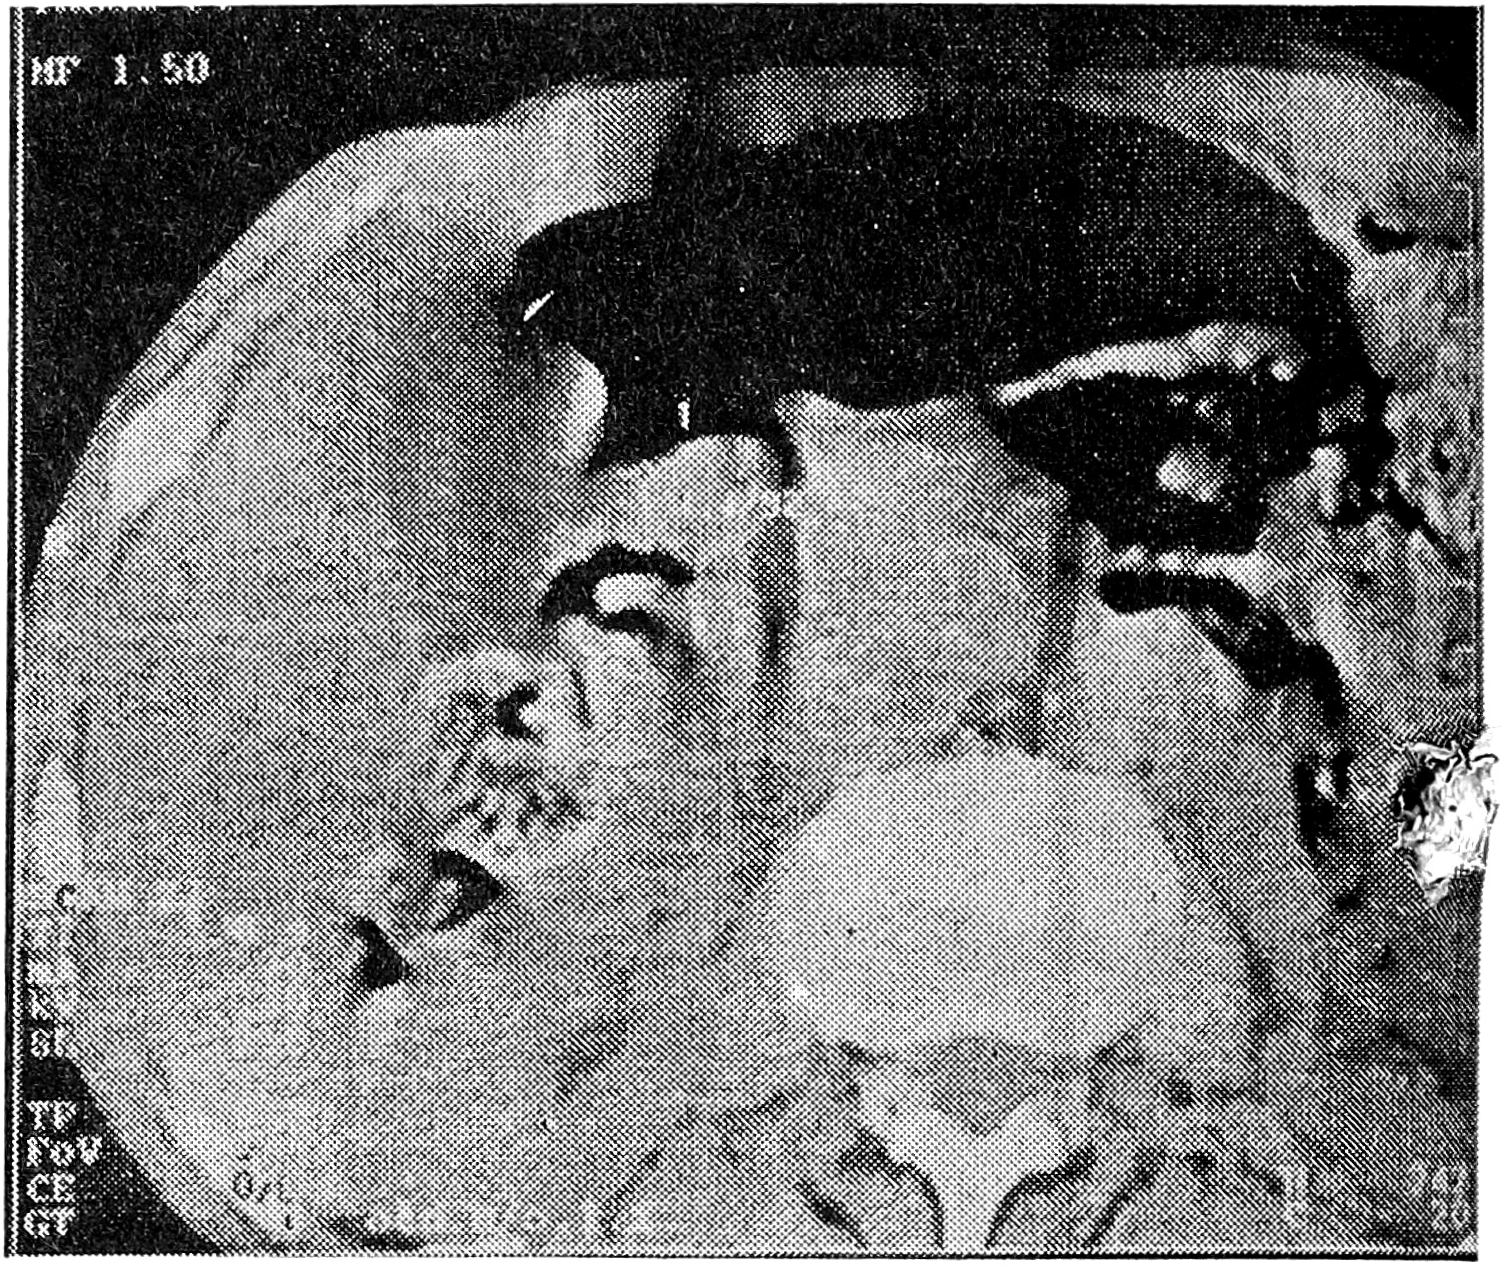

Исследование показало, что основным КТ-признаком эндофитного рака желудка можно считать утолщение его стенки в месте опухолевого поражения до 1 см и более (рис. 1). При опухолях небольших размеров (до 4-5 см) это утолщение носило локальный, ограниченный характер. Распространения процесса за пределы стенки желудка на соседние структуры не наблюдалось. Контур поражения был ровный, эластичность стенки нарушалась незначительно (рис. 2, 3). Отчетливую границу между пораженным участком и неизмененной стенкой желудка провести было трудно. При КТ-диагностике сравнительно небольших по размерам эндофитных опухолей желудка (вызывающих затруднения как при классическом рентгенологическом, так и при эндоскопическом исследованиях) необходимым условием являлась сравнительная оценка толщины стенки желудка на ограниченных участках с соседними неизмененными участками. Даже незначительное утолщение ограниченного участка стенки (до 7-8 см) при наличии других рентгено-эндоскопических признаков эндофитного поражения являлось дополнительным критерием, подтверждавшим эндофитный рак желудка. К достоинствам КТ необходимо отнести возможность обнаружения в процессе исследования гионарных и отдаленных метастазов, которые встречались достаточно часто даже при небольших по размерам опухолях желудка.

Рис. 1. КТ желудка больной С., 59 лет. Эндофитный рак кардиального и субкардиального отделов желудка. Определяются утолщение стенок кардиального и субкардиального отделов желудка до 1,4 см, некоторая неровность внутреннего контура.